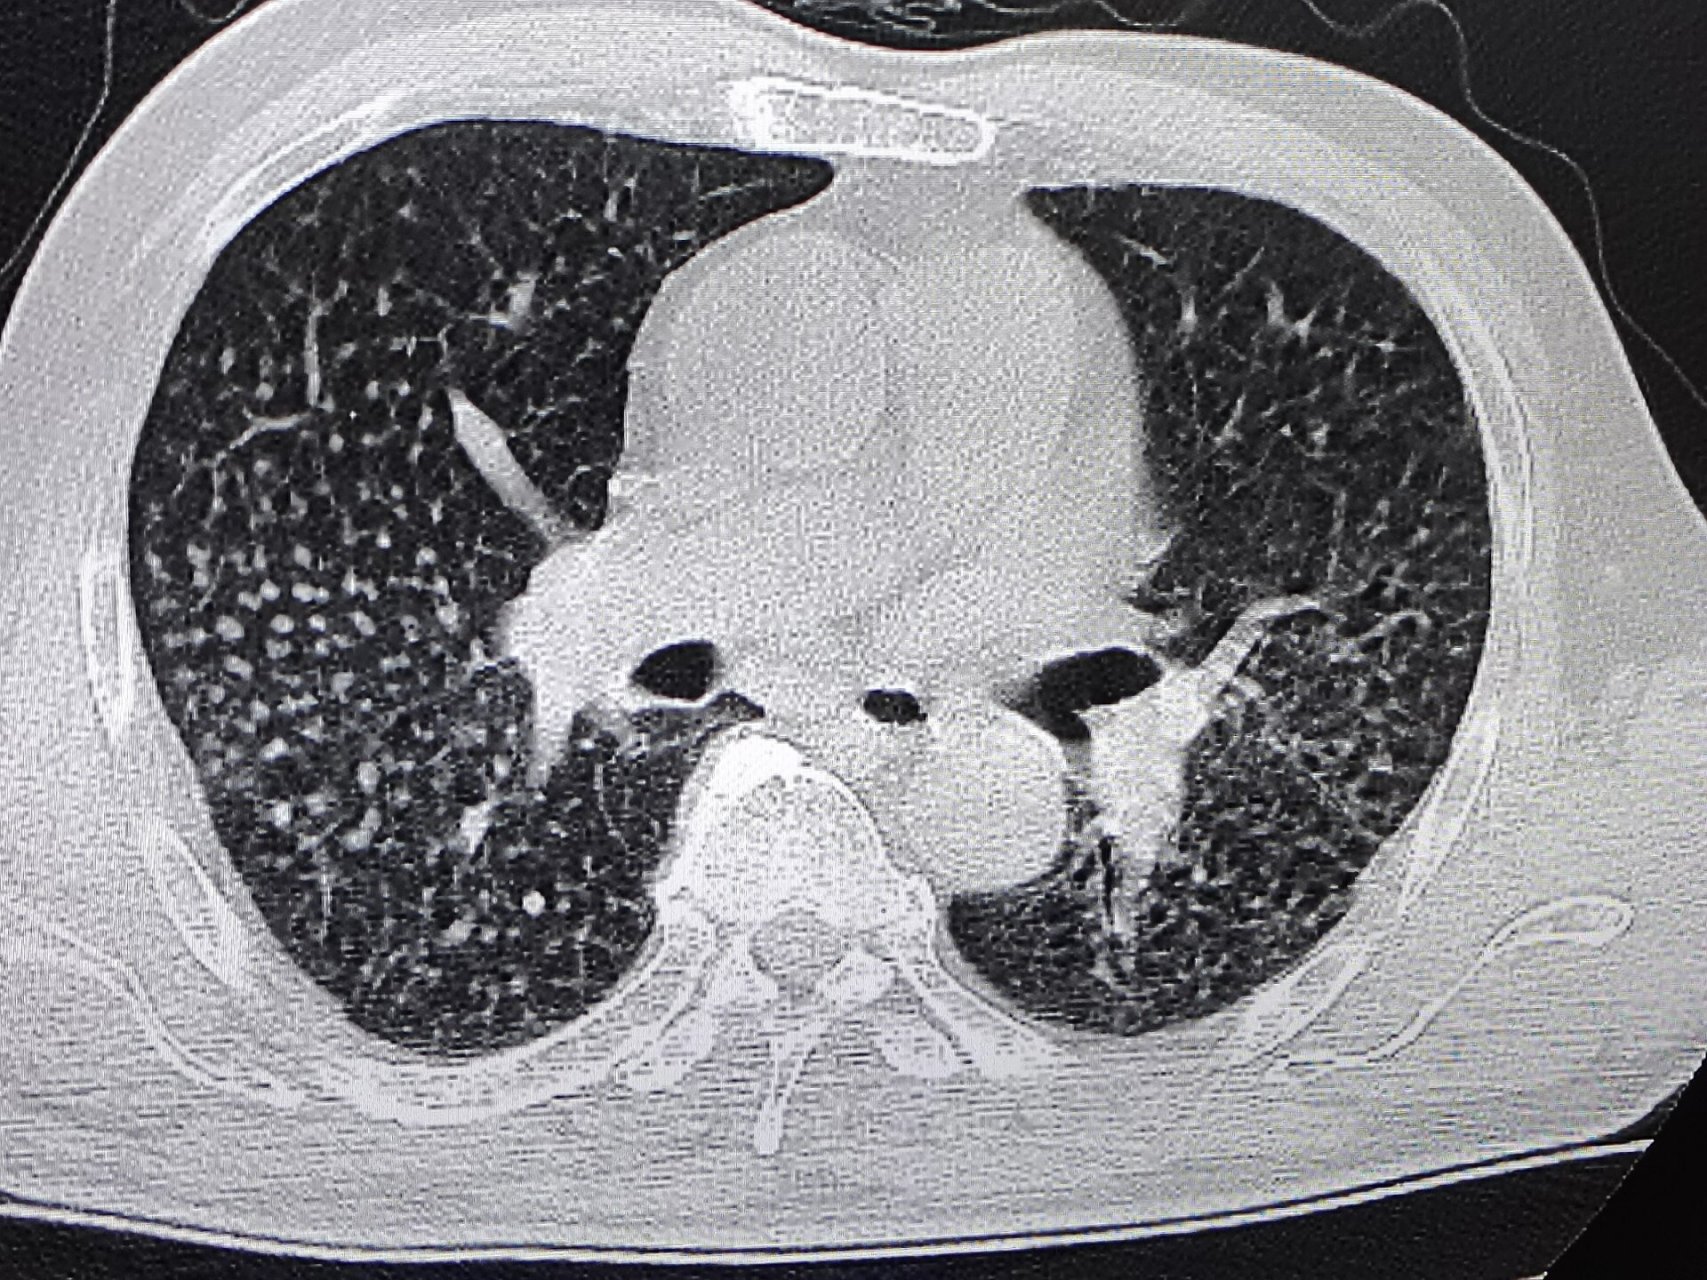

矽肺ct表现 两肺见弥漫多发粟粒结节影,可以看到两肺门,纵隔淋巴结轻

早期矽肺ct特征表现为双肺多发,无融合的小结节影,大小不等,多为2